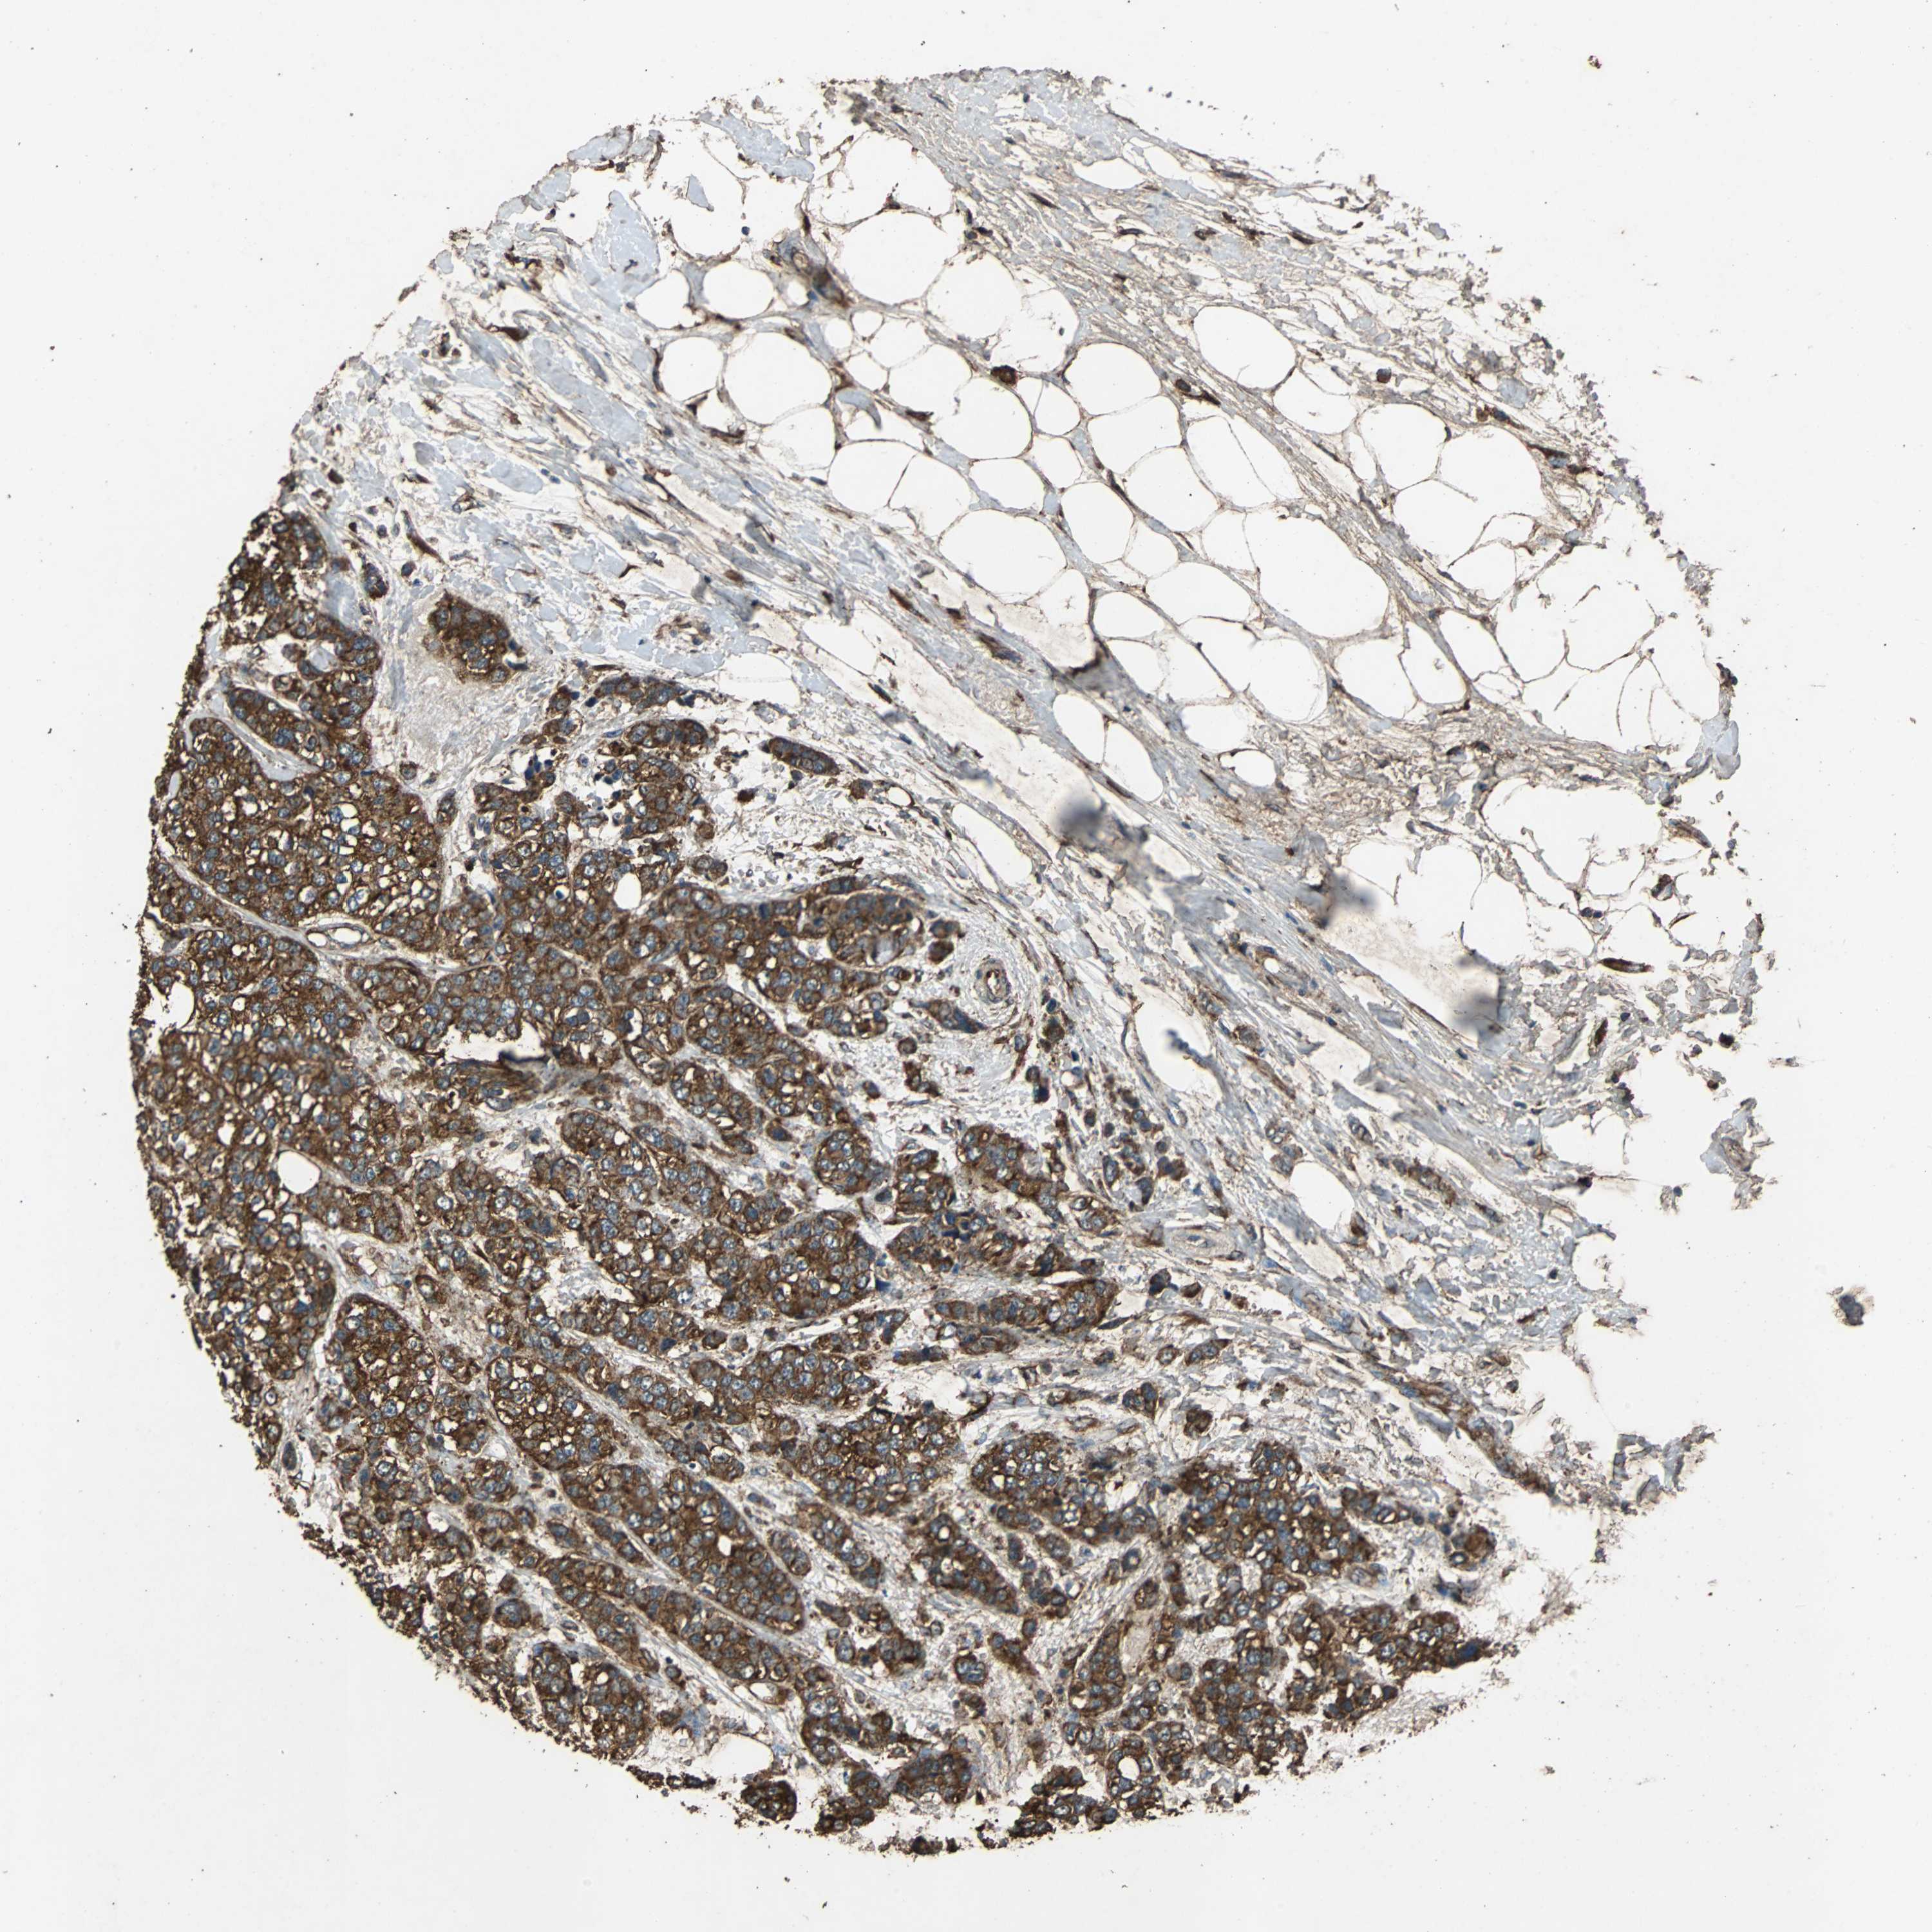

CANCER BREAST CANCER Show tissue menu

BRCA TCGA BRCA VALIDATION PROTEIN EXPRESSION

ANTIBODIES

AND

VALIDATION